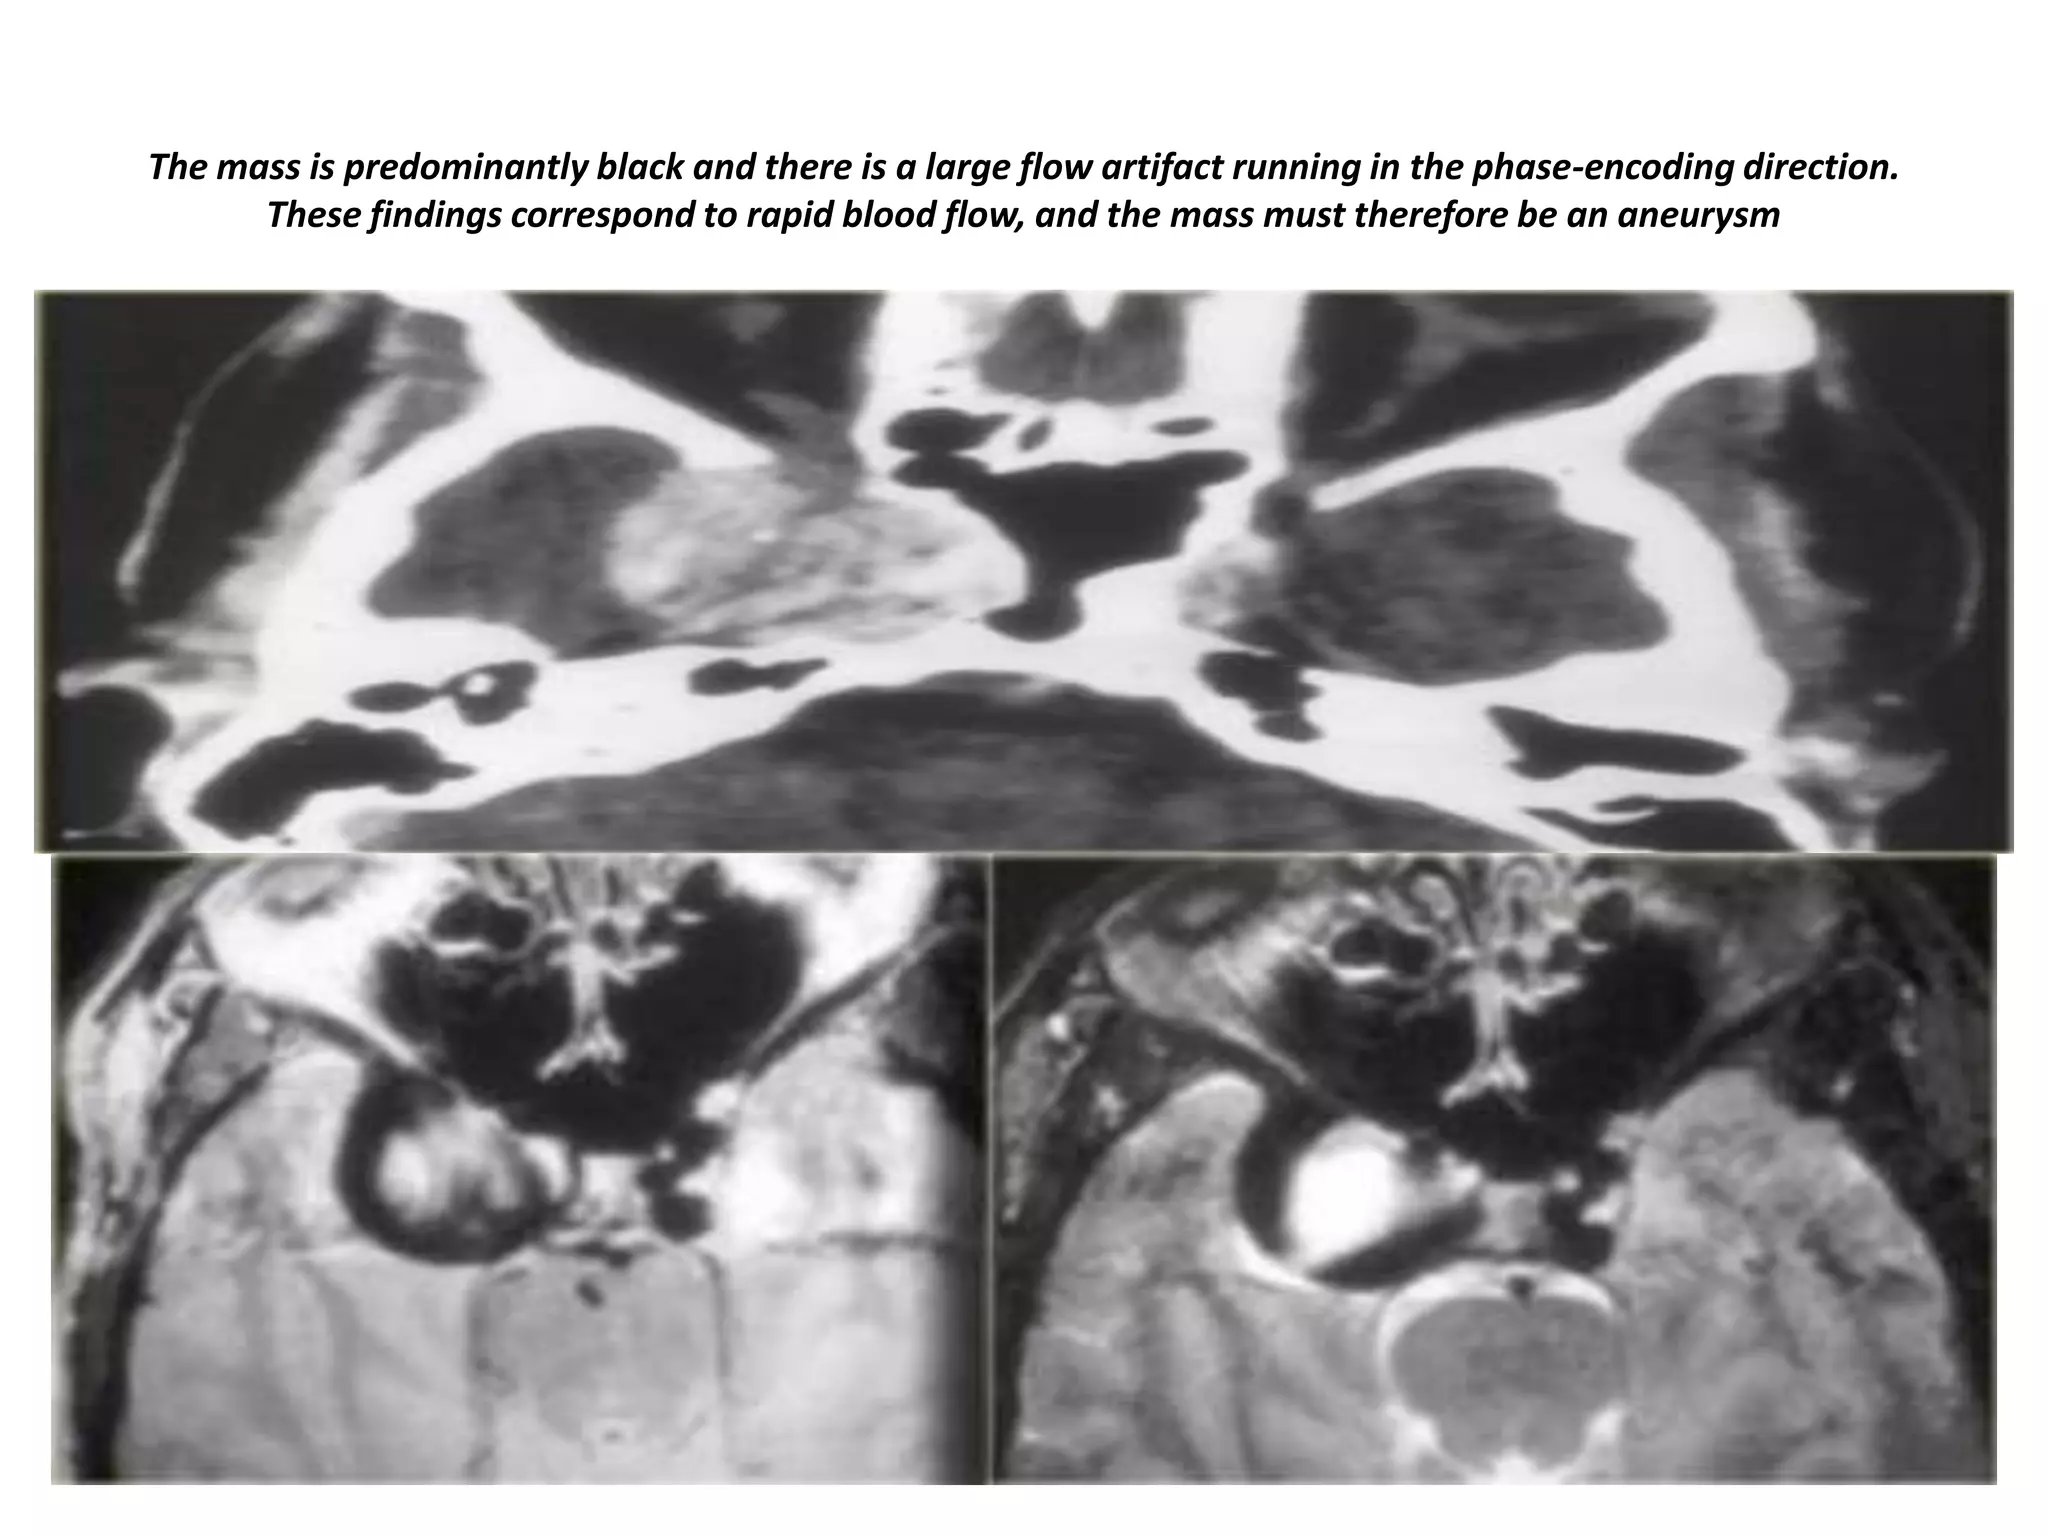

Right para-sellar partially thrombosed aneurysm.

Aneurysm of right para-sellar region with partially thrombosed aneurysm.

Enhanced and non-enhanced study of right para-sellar aneurysm.

The mass is predominantly black and there is a large flow artifact running in the phase-encoding direction.

These findings correspond to rapid blood flow, and the mass must therefore be an aneurysm